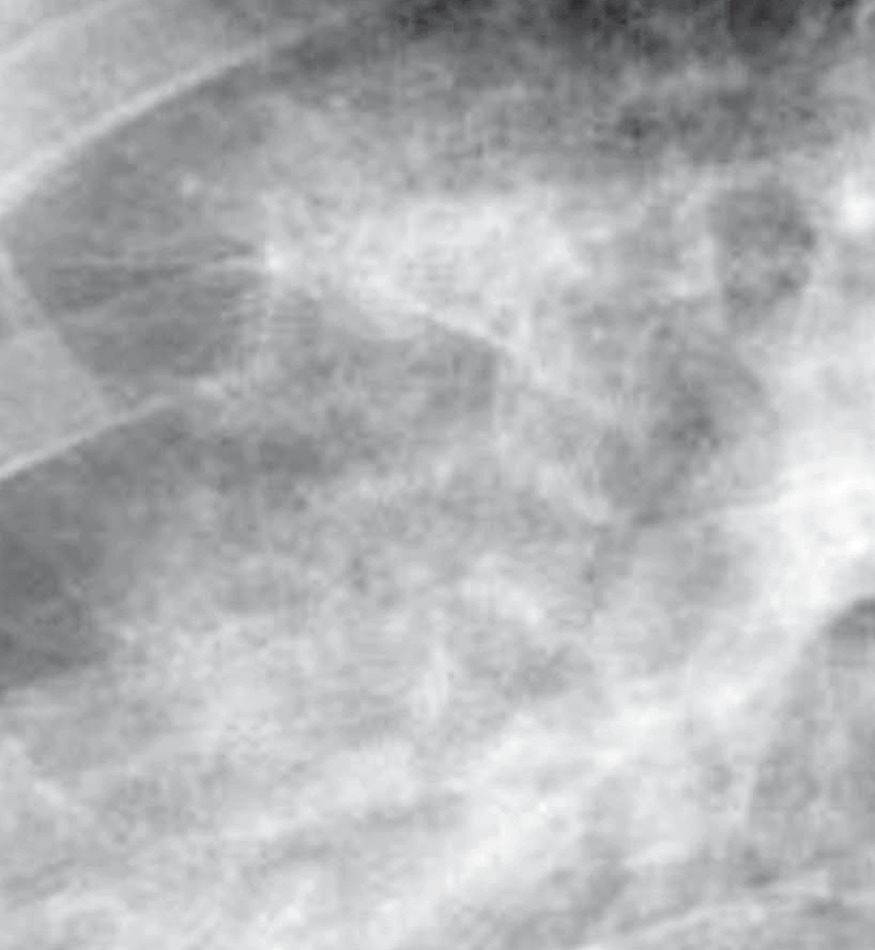

图2-2 实变:边界不清的,毛玻璃样致密影伴“肺泡充气征”

放大影像细节观察右肺下叶实变呈磨玻璃样边界不清的致密影,内含有小圆形透亮影,称为肺泡充气征,尽管与实际肺泡大小并不相符;B.右下叶肺炎患者胸部CT显示边界不清的磨玻璃样实变(白色箭头),实变区内小的局灶性透亮影(黑色箭头)为“肺泡充气征”

肺泡充气征

如果肺实变不融合,可以看到间杂小的局灶性透亮区,代表未受累的肺组织( 图2-2)。这些透亮区被称为“肺泡充气征”,但因为肺泡太小无法在X 线片上看到,这是一个误称。这些透亮区反映了不完全肺实变。